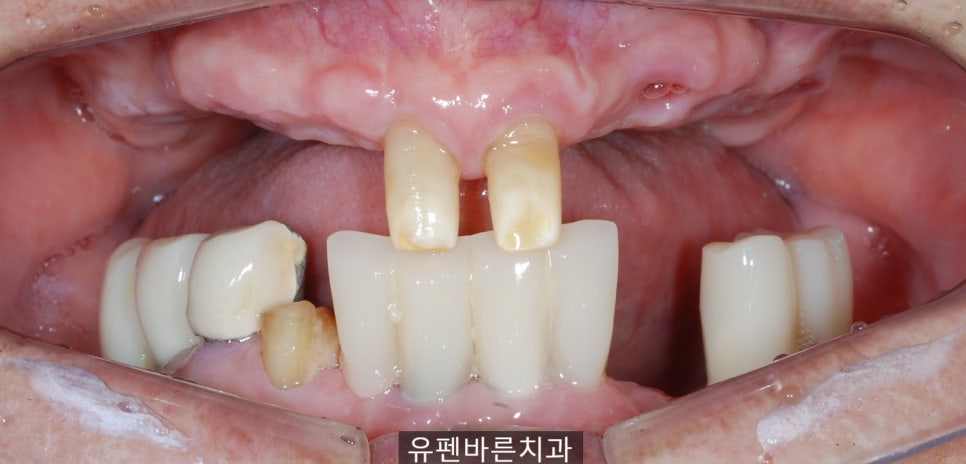

엑스레이 촬영 결과

교합이 맞지 않고,

왼쪽위의 브릿지는

흔들거리고

치아들이 정출되어

위 앞니가 내려와

아래 잇몸에 닿고 있는

상태셨어요,,,

남아있는 치아들 마저

보철물 안쪽으로

충치가 심해

발치를 해야 하는

상황이었습니다..

먼저

잇몸 절개 후

뼈 상태가 양호한 곳에

임플란트 위치를 잡고

수술을 시작하셨는데요,

10개월에 걸쳐 진행된

임플란트

수술인 만큼

다들 궁금해 하실테니

전후 사진

바로 보여 드릴게요 :)

상악에 6개, 하악에 8개

총 14개의

임플란트 수술을

잘 마쳤습니다.

임플란트들이

아주 예쁘게

잘 심어진 것 같죠?

잇몸에 닿았던 앞니가..

맞물리는 치아가 생기고,

무너져 있던 교합이

바로잡아지면서

환자분께서

식사를 잘 하실 수 있게

되셨어요 .